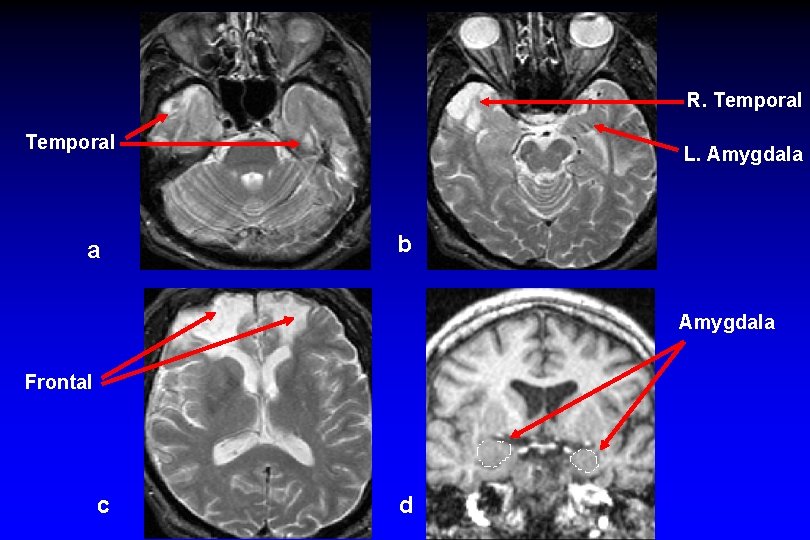

Emotion and Cognition • Amygdala is a small almond-shaped structure, just anterior to the hippocampus; it is located in medial temporal lobe • Although amygdala is specialized in processing emotion, it is now recognized that amygdala influences cognitive processes and is influenced by cognitive processes • Thus, both cognition and emotion need to considered in context of each other

Emotion and Cognition • Amygdala and related brain structures

R. Temporal a L. Amygdala b Amygdala Frontal c d